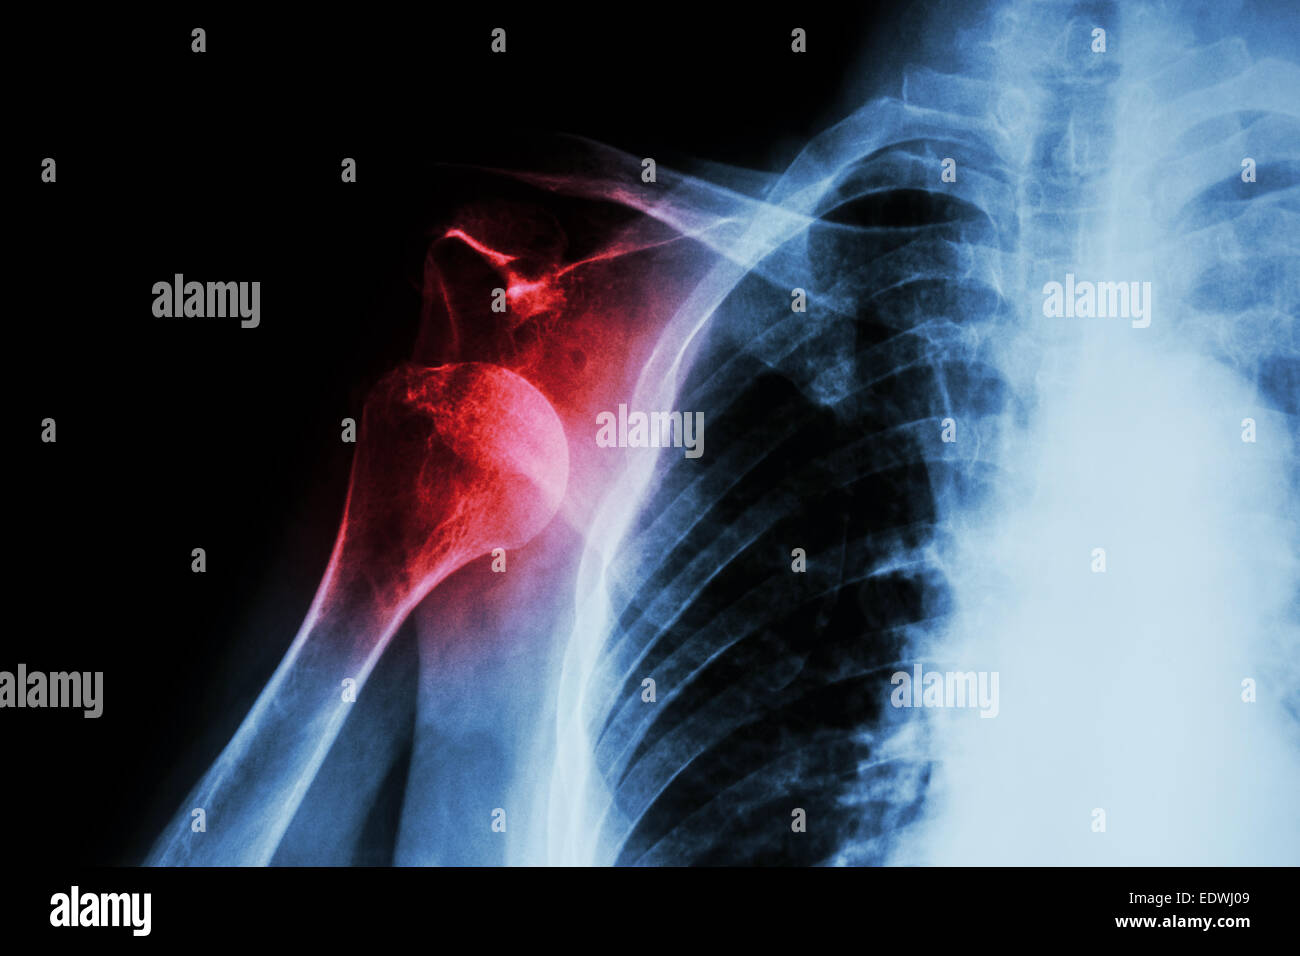

Anterior Shoulder Dislocation X Ray HopeanceHawkins

Dislocated shoulder, Xray Stock Image C039/3327 Science Photo Library X Ray For Shoulder Dislocation They not only confirm whether a dislocation. Injury to the axillary nerve during shoulder dislocation is as high as 40%. A health care provider inspects the affected area for tenderness, swelling or deformity and checks for signs of nerve or blood vessel. Often, it is important to evaluate the ligaments, and a magnetic resonance imaging (mri) scan is helpful in. X Ray For Shoulder Dislocation.